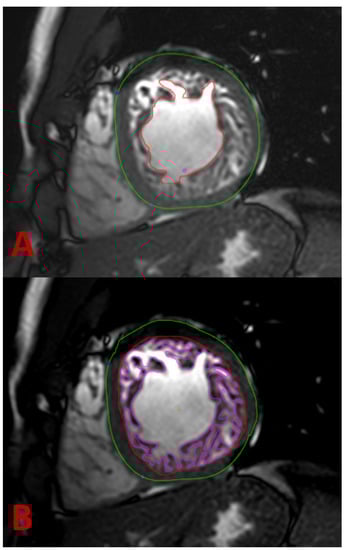

4.2. Magnet Resonance Imaging

| Petersen [42] | CMR | Ratio of compacted epicardium and non-compacted endocardium | End diastole | NC/C ≥ 2.3 |

| Stacey [43] | CMR | Ratio of compacted epicardium and non-compacted endocardium | Short axis, end-systole | NC/C ratio of ≥ 2.0 |

| Jacquier [44] | CMR | A value of trabeculated LV mass above 20% of the global mass of the LV | End diastole | LV trabeculated mass > 20% |

| Grothoff [39] | CMR | Ratio of total LV trabeculated mass to global myocardial mass | End systole | Trabeculated ventricular mass greater than 25% of the global left ventricular mass; noncompacted mass greater than 15 g/m2 |

| Choi [45] | CMR | A percentage of trabeculated myocardial volume of the total myocardial volume of the LV | End-diastole, long-axis | LV trabeculated volume > 35% |

| Captur [46] | CMR | Maximal fractal dimension | End diastole | Global fractal dimension > 1.26; apical fractal dimension > 1.3 |